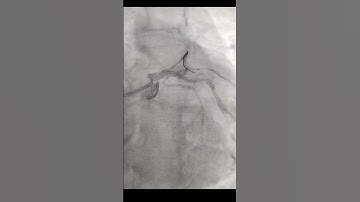

EBC 2025 - Session 1A - Pitfalls & Troubleshooting in Nailing the Ostium in Coronary Bifurcations